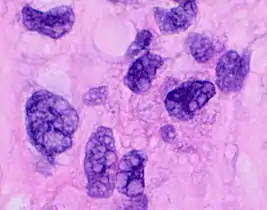

- Pleomorphic when having different sizes and shapes. This often correlates with an increased nucleus to cytoplasm ratio. These features generally indicate malignancy.